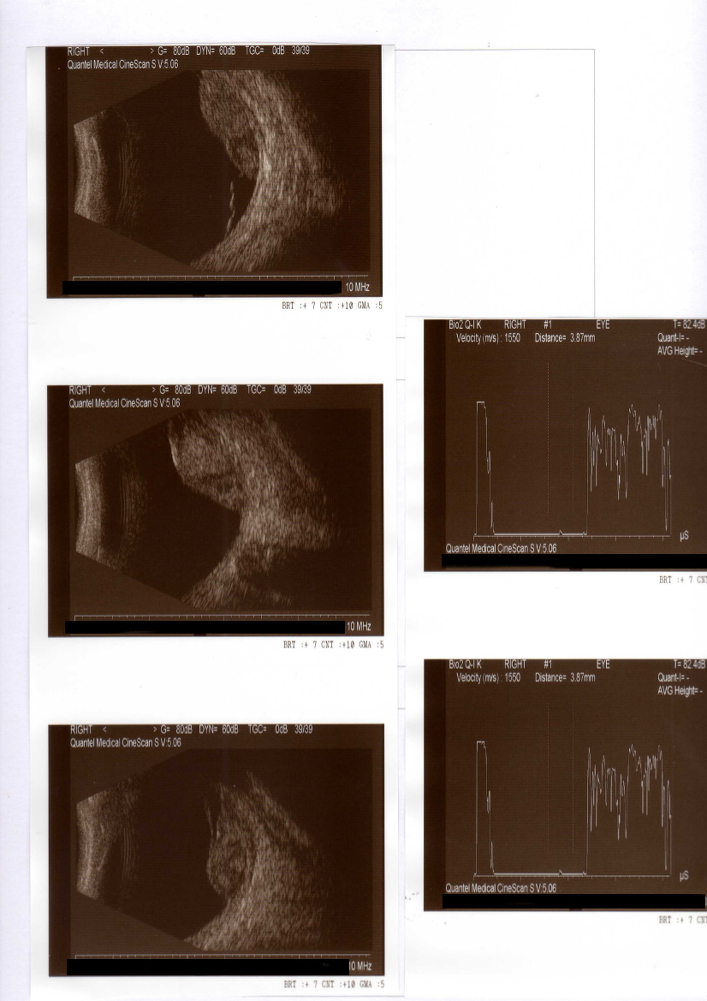

8 Neoformazione (tumore) oculare

Paziente di 68 anni effettua visita oculistica per lieve calo visivo occhio destro, l'obiettività oculistica riscontrata è la seguente:

vod: 9/10 con correzione ottica

vos: 10/10 con correzione ottica

too: 18

tos: 16

boo: sclerosi del cristallino

fod: neoformazione coroideale settore inferiore

fos: nei limiti di norma

Richiesta ecografia (vedi allegato): confermata la presenza di neoformazione coroideale con sospetto di neoplasia secondaria.

La paziente è stata inviata presso un centro specializzato per un opportuno inquadramento sistemico della patologia con esami, ad esempio come la TAC total body per valutare la presenza di una neoplasia primaria che abbia potuto dare metastasi all'occhio. In presenza di sospetta neoplasia secondaria dell'occhio il paziente deve essere gestito da un centro oncologico per una corretta diagnosi tesa ad identificare la neoplasia primaria e la conseguente terapia più idonea.